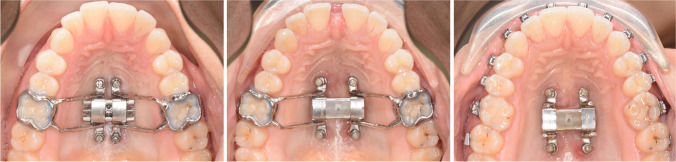

Fig. 3.

Frontal view of an intra-oral scan with D-MED at T0 (A: left) and T1 (B: right)

Maxillary expansion was initiated immediately after insertion of the D-MED (see: Fig. 4a). The screw was activated once a day, equivalent to 0.25 mm, and the expansion was closely monitored with weekly check-ups. The expansion was measured intra-orally with a digital calliper at the expansion screw, the central diastema, and inter-molar and inter-canine widths, and periodontal pockets deeper than 3 mm around the upper central incisors were recorded. The expansion was considered successful when the occlusal aspect of the palatal cusp of the upper first molars contacted the occlusal aspect of the buccal cusp of the lower first molars, and thus, when the necessary amount of expansion was achieved. The expansion screw was then blocked with resin-based composite. According to the retention protocol, the D-MED was left in place for 3 months after the end of expansion to allow remodelling of the bone in the separated midpalatal suture (see: Fig. 4b). After 3 months, the bands and connectors were removed and the treatment could be continued with a fixed straight-wire appliance, while the four miniscrews and the expansion screw were left in place for retention (see: Fig. 4c). The patients were then seen for a retention check-up at 6 and 12 months after termination of expansion. Finally, the expansion screw and miniscrews were removed either at 12 months or, in case of a surgical orthognathic treatment, prior to surgery.

Fig. 4.

Maxillary occlusal view with D-MED at T0 (A: left), T1 (B: middle), and 3 months after expansion (C: right)